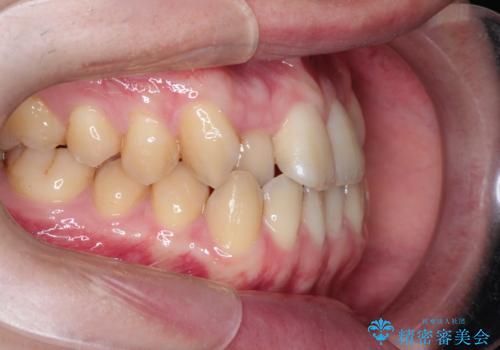

前歯のデコボコ インビザラインによる目立たない矯正

- 前歯のデコボコを主訴に来院された患者様です。

目立たないそうちをご希望されたので、インビザラインにて治療することとしました。

歯と歯の間をわずかに削ってスペースをつくり、デコボコを改善しました。